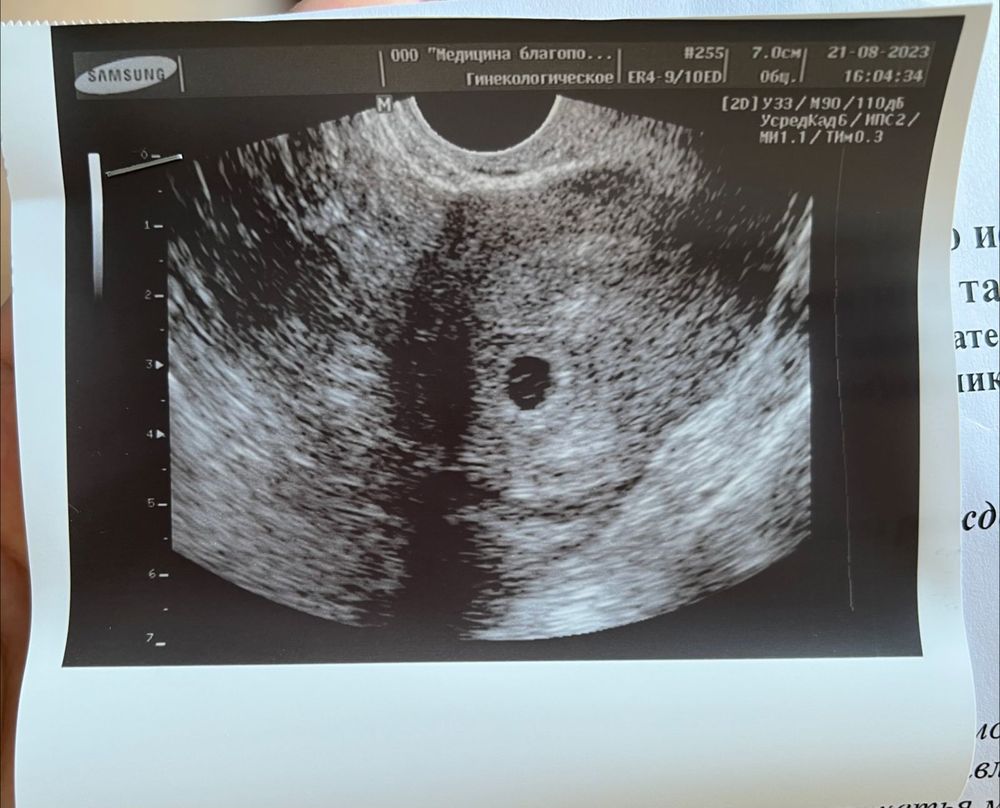

5 недель и 6 дней по М УЗИ

Овуляция была где то на 18-19 ДЦ. Вчера пошла узи, все там хорошо, кроме одного-пока не видят эмбриона. Говорит, по идее уже сердцебиение должно быть. Возможно, было позднее прикрепление. Я что то волноваться начала. Никакие диагнозы не ставят, сказали подойти через 7-10 дней на контрольное узи. Потом вставать на учет по беременности. Девочки, подскажите, у кого так было? Малыша нашли? Это вторая беременность. Первая зб. Ставят маточную беременность малого срока(со слов врача, недели 4)

Рано ещё для эмбриона,у вас если смотреть по первому хгч,он соответствует примерно 9-10 дпо,т.е сегодня 24-25 дпо,а это 3,3 от зачатия и 5,3 акушерских,по месячным больше,но и овуляция позже была,через неделю эмбрион должен быть,а пока узи соответствует вашему реальному сроку